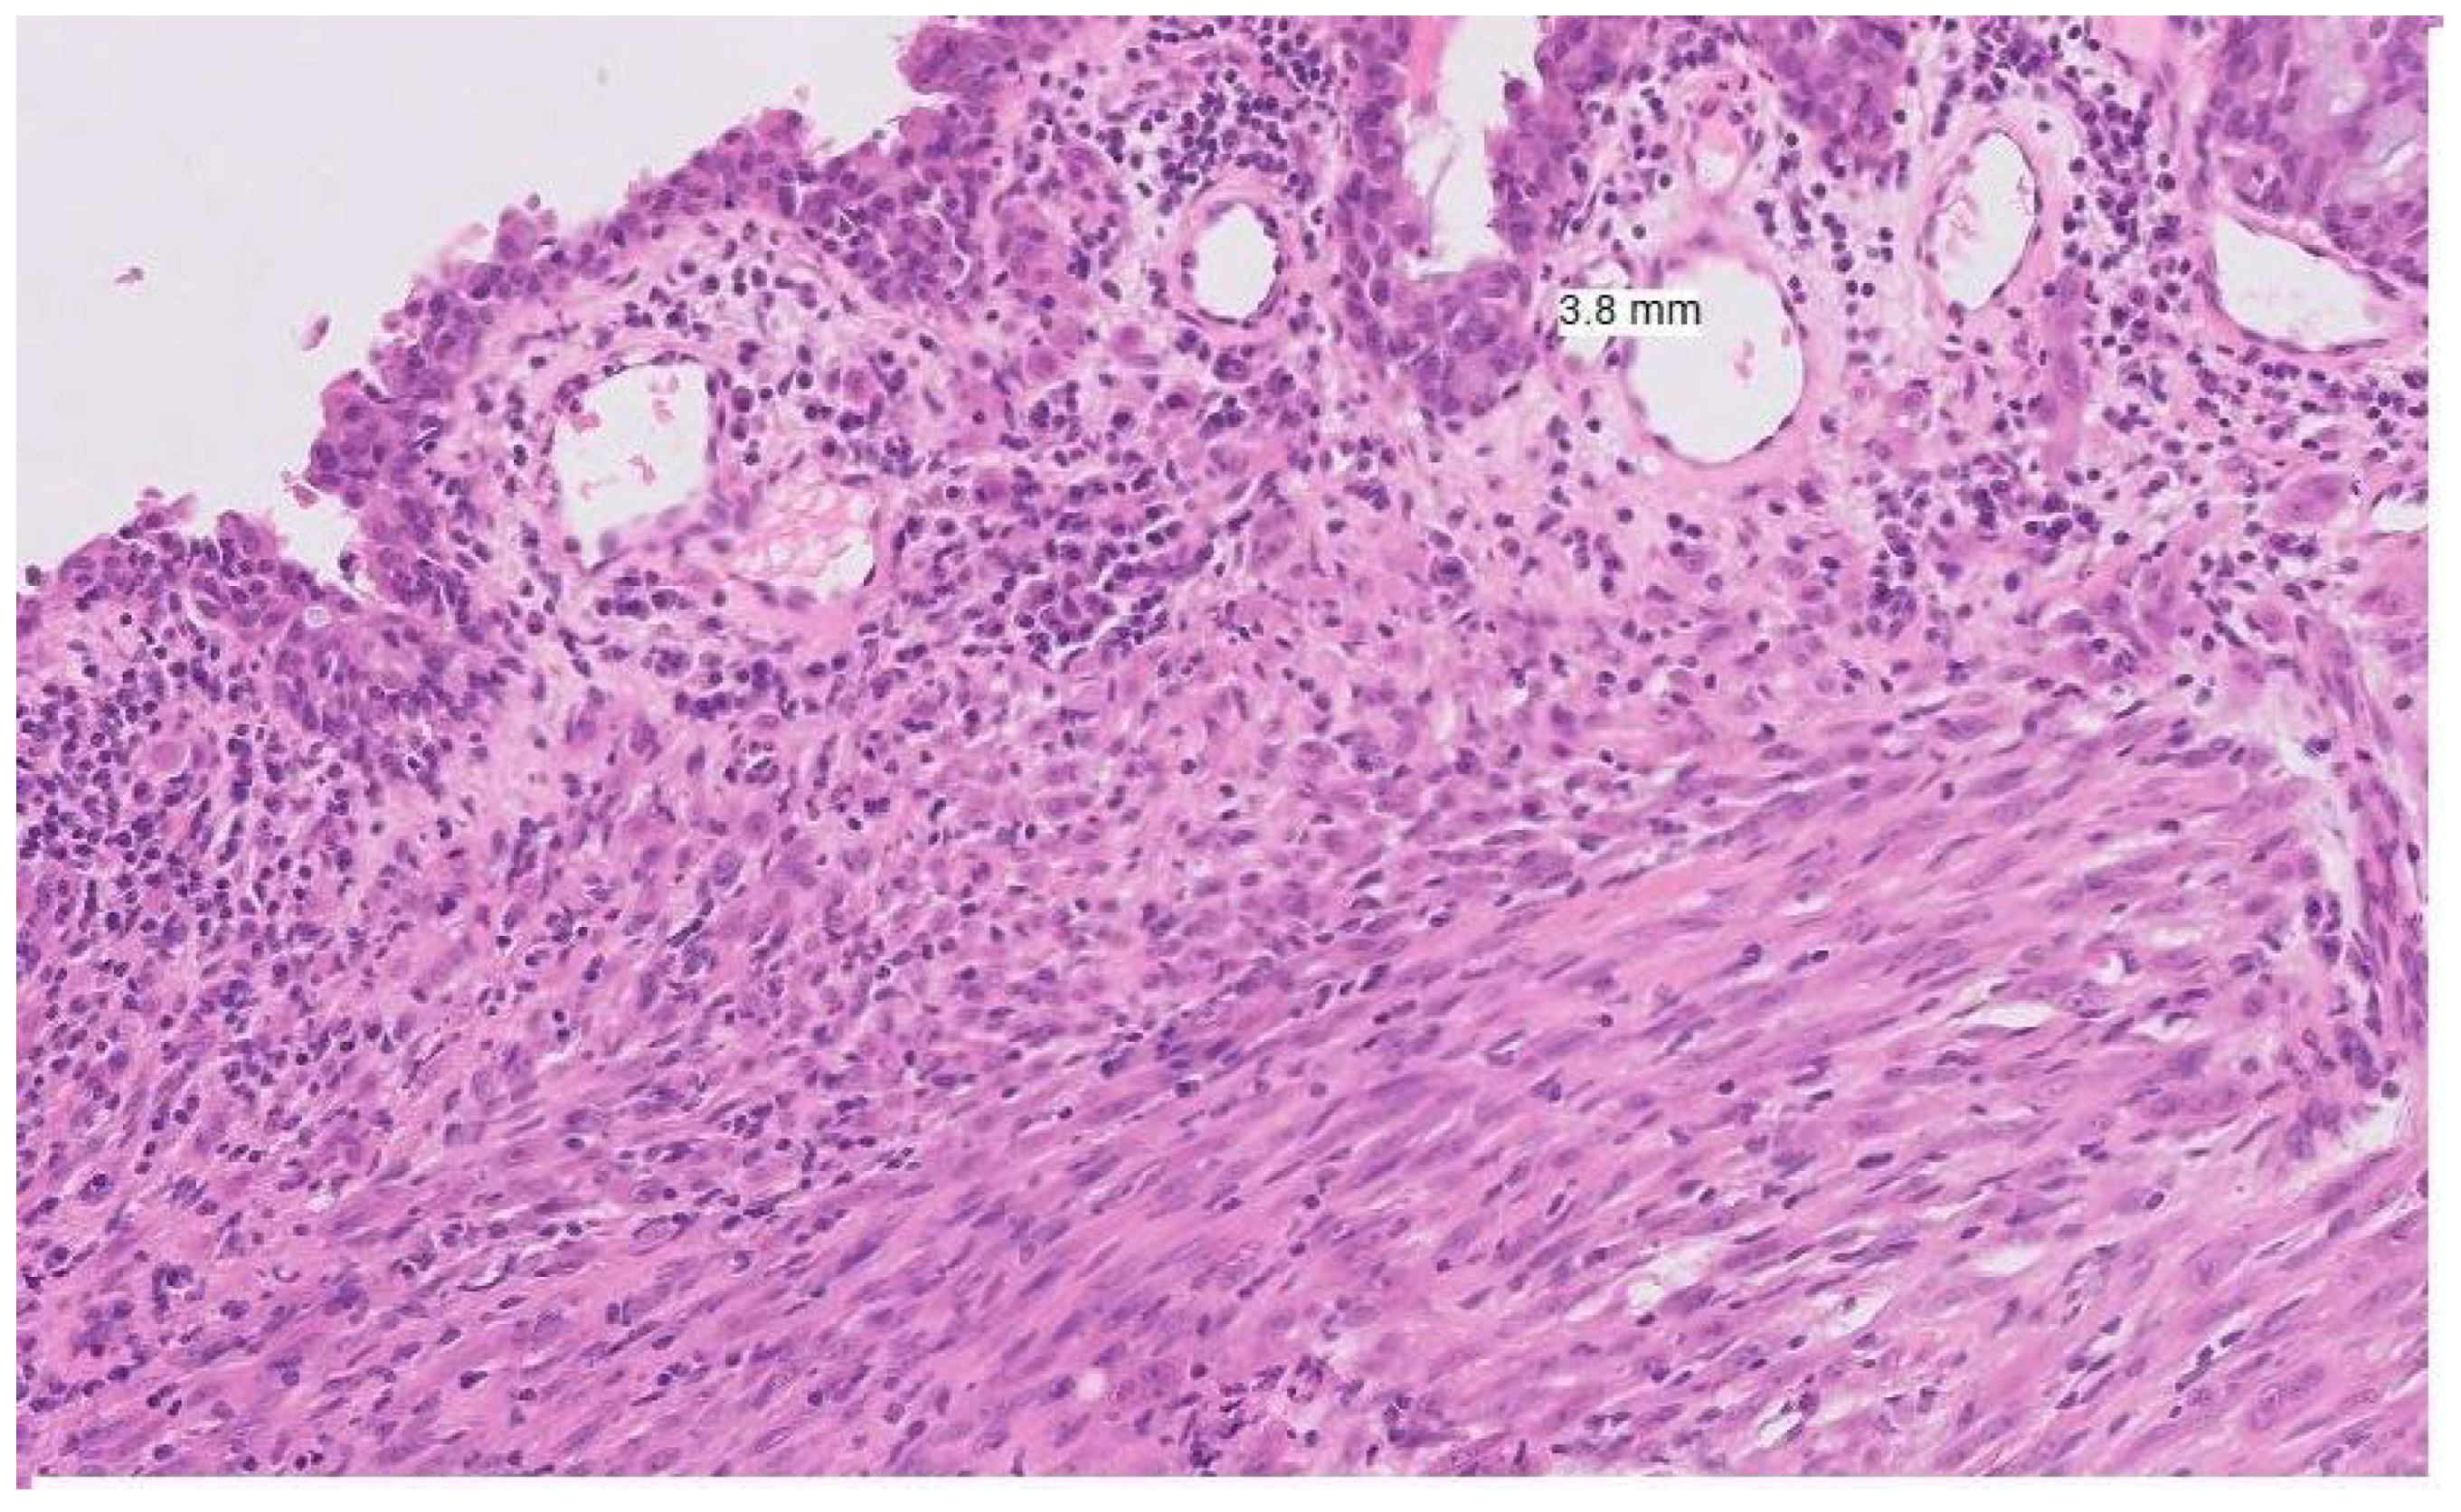

Figure 1. Histopathological image of mucosal melanoma showing atypical melanocytes infiltrating the submucosa.

Mucosal melanomas are less immunogenic and generally have a lower tumour mutational burden, particularly those arising in the anorectal and urogenital tracts compared with conjunctival or nasal sites [16,20]. This site-specific variation may partly reflect the mutagenic role of UVR, which influences the distinct mutational signatures of mucosal melanomas in facial sites compared with those in the lower body [20]. The tumour immune microenvironment in mucosal melanomas also shows reduced immune cell infiltration and a weaker interferon-gamma signature compared with cutaneous melanoma—a difference that is especially marked in urogenital tumours compared with those of the head and neck [21] (See Figure 1). The above distinct genetic alterations and lower immunogenicity with low tumour mutational burden contribute to reduced efficacy of systemic therapies and ICIs. These factors combined with delayed and late diagnosis, significant heterogeneity within the mucosal melanoma group and challenges of surgical resection, contribute to the aggressive nature of this tumour group.